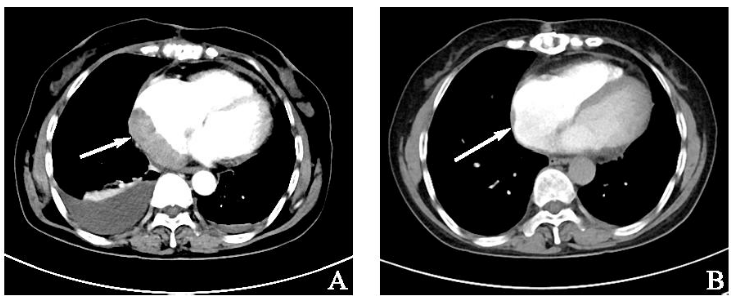

术后返院进一步治疗,心电图示房颤,骨髓细胞学示三系增生,未见异型淋巴细胞浸润。头颈部、胸部、全腹增强CT未见淋巴瘤浸润转移。经多学科会诊后建议术后化疗,予以8R+6-8CHOP方案化疗(利妥昔单抗500 mg d0+环磷酰胺1 g d1+表柔比星100 mg d1 +长春新碱1.9 mg d1+泼尼松100 mg d1~5)。经3周期化疗后相关影像学检查疗效评价部分缓解(图3 B),但患者后续未返院继续化疗。

1736904234150760.png

图3 术后及化疗后影像学检查。注:A:术后45 d胸部CT(2021年3月20日);B:化疗3周期后胸部CT(2021年6月6日)